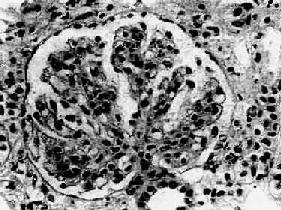

肾小球系膜细胞和基质增生。系膜区增宽,其间常有数量不等的中性粒细胞浸润。增生的系膜组织逐渐向周围毛细血管伸展,侵入毛细血管基底膜与内皮细胞之间,使毛细血管壁增厚,管腔狭窄(图12-13)。应用银染法可见增厚的毛细血管壁呈车轨状或分层状。由于系膜增生,系膜区增宽,使毛细血管丛呈分叶状。严重时可使轴心处呈结节状。病变继续发展,增生的系膜组织可环绕全部毛细血管壁,使管壁显著增厚,管腔狭小甚至阻塞。有时部分肾小球内可有新月体形成。晚期,系膜及肾小球纤维化、硬化,整个肾小球形成无结构的玻璃样小团。相应的肾小管萎缩,间质纤维组织增生,有多数淋巴细胞及单核细胞浸润。

图12-13 膜性增生性肾小球肾炎

肾小球系膜细胞增多,增生的系膜组织侵犯毛细血管,毛细血管壁增厚,腔狭小,肾小球丛呈分叶状